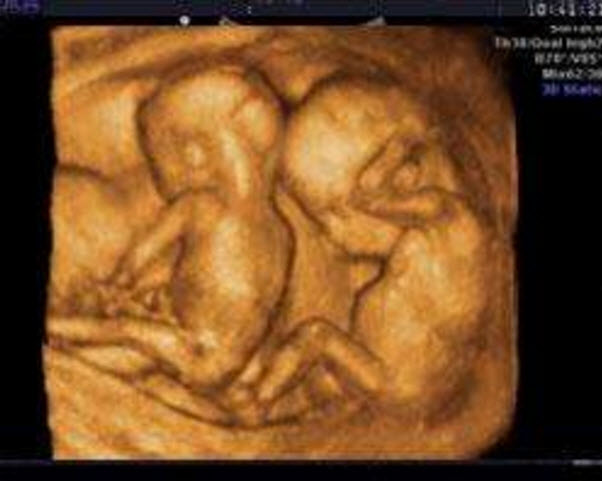

超聲波檢查檢測到兩個(gè)胎心波

超聲波檢查檢測到兩個(gè)胎心波是最明顯的懷雙胞胎的癥狀。如果懷了雙胞胎,那么用超聲波檢查就可測到兩個(gè)不同速度的胎心波,同時(shí)用X線檢查也會顯示兩個(gè)胎兒的骨骼。